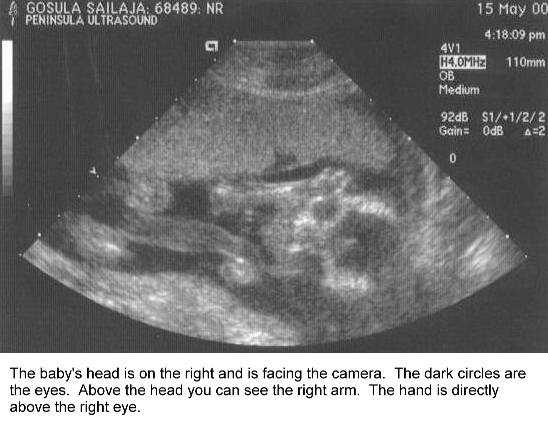

B18weeks.jpg